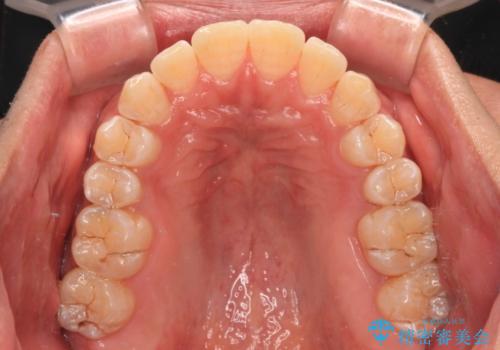

- 前歯のデコボコを気にして来院された患者様です。

インビザラインによるマウスピース矯正も適用となる歯列でしたが、できる限り自己管理の煩わしさのない状態で治したいとのことで、ワイヤー装置にて矯正治療を行うこととしました。

予定していた期間より長くかかりましたが、1年強できれいな歯列に仕上がりました。